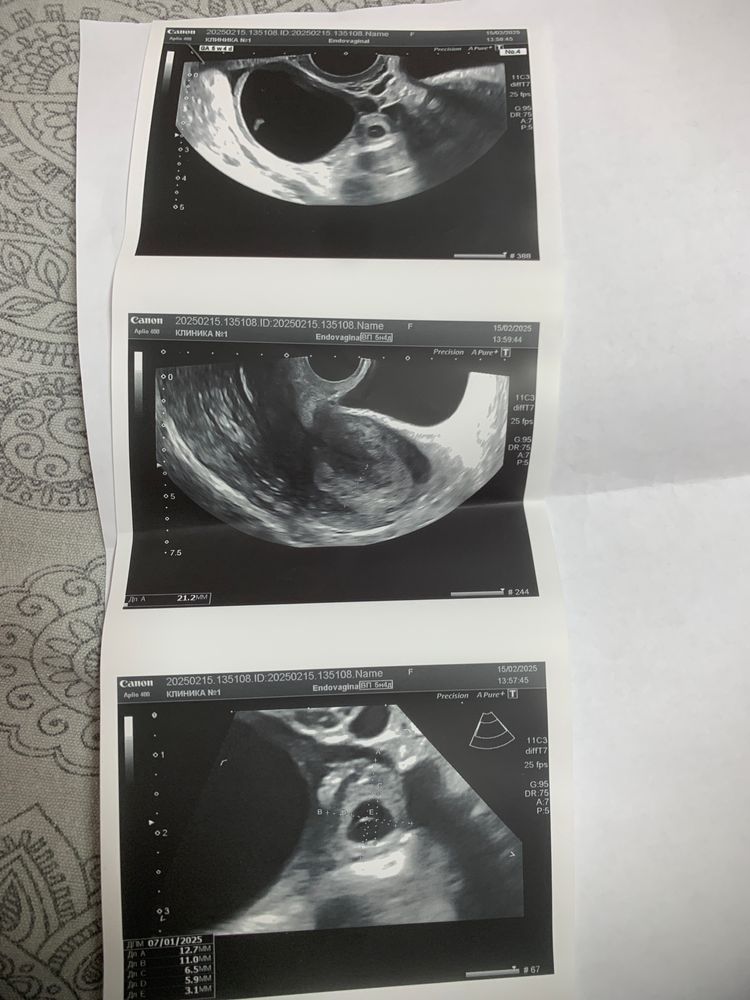

Внематочна

Светлана , у меня в правой трубе(трубу вырезали,сейчас планирую дальше с одной (

Светлана , получается у вас вторая внематочная?

Светлана , мне врач сказала что вторая труба на вид хорошая по этому не видит смысла ее продувать.но внутри ее не смотрели.в этом месяце уже планировали в овуляцию малыша.в конце месяца будем ждать результам) но я всё же боюсь что опять это может повториться лучше бы я не слушала врача и пошла сама и проверила трубу.теперь жалею что не проверила и рано запланировали без проверки (((

Когда выйдет толстый эндометрий после внематочной? Через какое время после удаления трубы вы перестали предохраняться и через сколько забеременели?